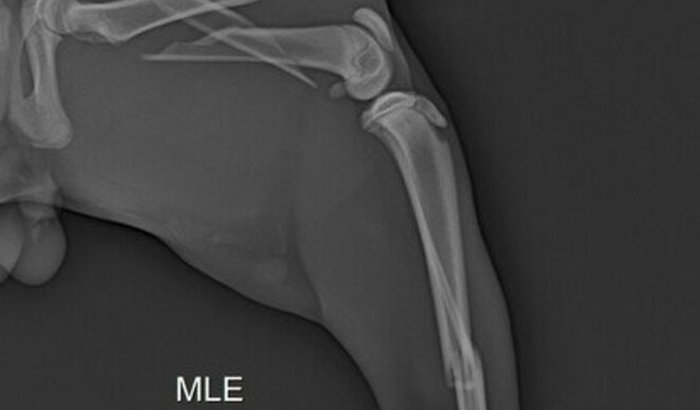

Olá, sou a dona do jubiscleu e venho aqui  pedir ajuda, pois ele foi atropelado e não tenho condições de pagar a cirurgia dele, ele quebrou a perninha em 3 lugar e está solta a perna dele, já procurei ajuda e não tem oq fazer, o caso dele é ver tudo

Olá, sou a dona do jubiscleu e venho aqui  pedir ajuda, pois ele foi atropelado e não tenho condições de pagar a cirurgia dele, ele quebrou a perninha em 3 lugar e está solta a perna dele, já procurei ajuda e não tem oq fazer, o caso dele é somente cirurgia com um ortopedista. quem poder ajudar agradeço de coração.